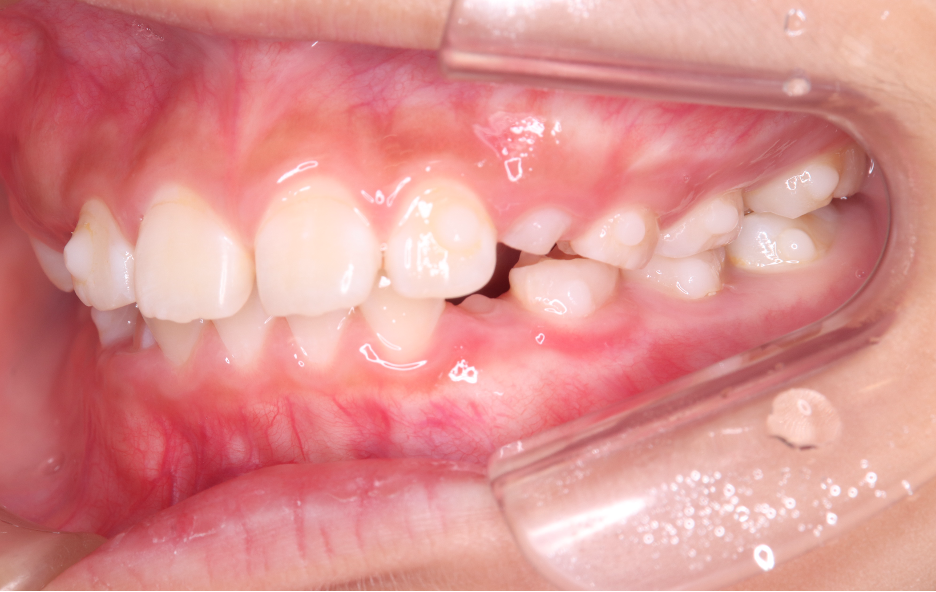

Before